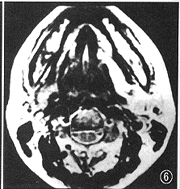

图6 MRI T2WI示左侧长条形肿瘤位于下颌舌骨肌与舌骨舌肌之间,与舌神经走向一致

2.肿瘤CT表现:(1) 大小为1.5 cm×1.0 cm~6.7 cm×6.5 cm;(2) 密度为较密集的小囊状低密度改变组成的筛样结构21例(图1),均匀密度7例,部分筛样、部分均匀密度5例;(3) 形态无定形20例(图2),类圆形11例,长条形与多结节形各1例;(4) 边缘不清晰20例,清晰13例,是由于周围正常脂肪组织环绕对比所引起;(5) 特殊改变:发生在气管的3例中,均表现为肿瘤绕气管腔后壁及两侧壁生长,以后部为主,管腔受压变形,但气管黏膜面仍保持光整(手术证实),甲状腺向两侧推移并均有累及(图3)。腮腺5例,同侧面肌和(或)颊肌呈萎缩改变者3例。发生在腭、鼻腔鼻咽、上颌窦等处肿瘤易侵犯翼腭窝向颅内浸润且合并颅底骨质破坏(5/10),其中侵犯中颅窝卵圆孔3例,表现为卵圆孔扩大或局部骨质破坏,同侧翼肌及咬肌萎缩(图4,5)。本组仅1例作MRI检查,发现肿瘤沿神经侵犯,表现为神经增粗(图6),此改变在CT上无法表现。

3.沿神经生长并侵犯神经:肿瘤容易沿着神经生长,可延伸至距主要瘤块相当长的距离,此改变CT表现有时不明确,而MRI则可比较清楚地反映此特点,表现为神经顺行或逆行增粗[6]。此种改变很少见于其他肿瘤,特征性强。如果肿瘤沿颅神经逆行生长,就易侵犯到颅内,并侵犯该神经(图7),引起神经症状(疼痛、麻木感)或相应神经支配的肌肉萎缩,从而间接显示神经受侵的改变,肿瘤侵犯颅神经提示预后不良[2]。